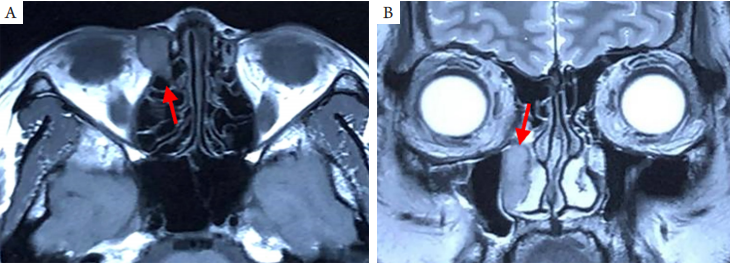

2.4 泪囊型

原发于泪囊和鼻泪管的淋巴瘤罕见,最常见的病理类型为MALT淋巴瘤和弥漫大B淋巴瘤。常见症状是溢泪、泪囊区肿胀、泪囊区肿块和泪囊炎症;体征是泪囊区可触及肿块和冲洗显示泪囊阻塞[19-20]。CT显示泪囊区或/和鼻泪管高密度占位、合并鼻泪管扩张增粗;MRI显示泪囊和鼻泪管病变T1WI和T2WI均为等信号(图4)。原发性泪道MALT淋巴瘤亦可见于儿童[21],临床应予重视。

20230619102640_9581.png

图4 泪囊和鼻泪管原发性MALT淋巴瘤的MRI表现

Figure 4 MRI findings of Primary MALT lymphoma in the dacryocyst and duct

(A)T1WI显示右泪囊区等信号占位;(B)T2WI显示右鼻泪管增宽,占位病变呈等信号。箭头示病变部位。

(A) Axial MRI shows the mass with isosignal in T1WI in the lacrimal sac area; (B) Coronal MRI shows the mass with isosignal in T2WI in the lacrimal duct. Arrows indicate the lession.